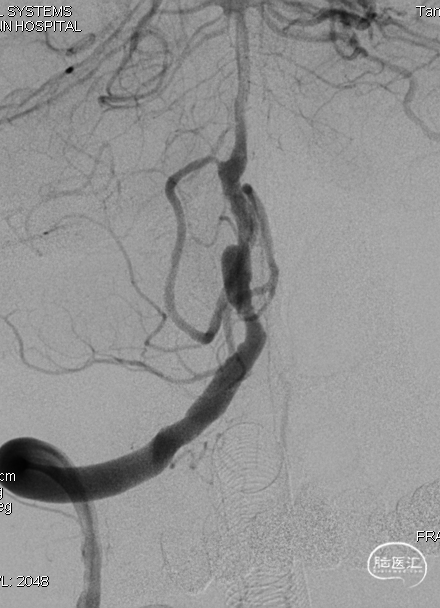

术后即刻DSA。

术后即刻稀释造影:“拉直”可见支架贴壁良好。

狭窄合并动脉瘤处理起来较为棘手,安全有效的扩张是手术成功必要的一环。

普通支架辅助栓塞梭形动脉瘤效果不佳,FD疗法能更好修复管腔,期待随访结果。